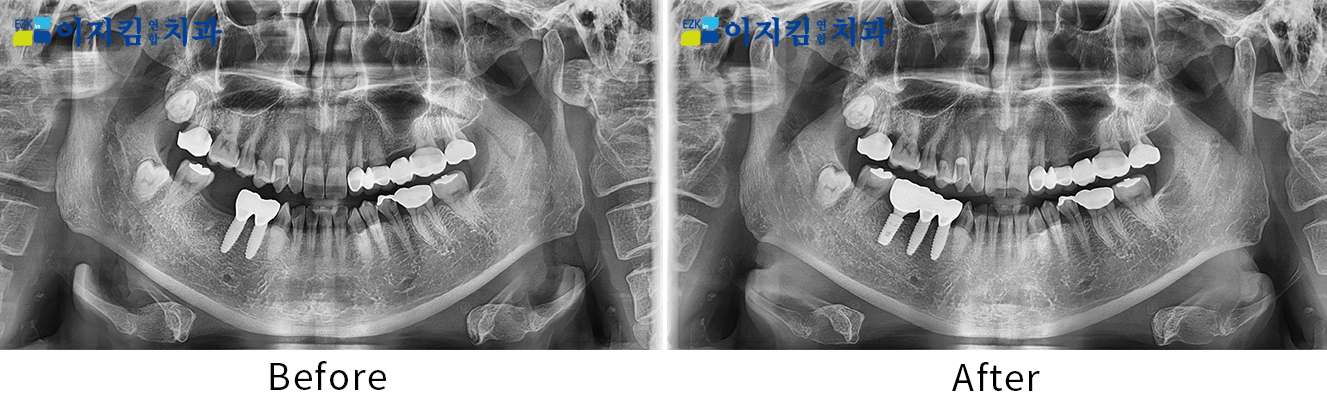

ÀÓÇöõÆ® Àü ¡¤ ÈÄ »çÁø

[

Á¶È¸¼ö : 3173

]